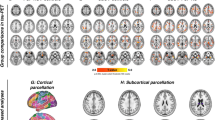

In total, 9870 functional connections among 141 ROIs were analyzed. PSP patients, compared to non-AD MCI reference group, expressed altered whole-brain functional network connectivity (NBS mass = 4350, pFDR < 0.05) (Fig. 1). The network consisted of 89 ROIs, including cortical, subcortical, and cerebellar nodes, and 118 connections among them. Details about single connections which the network is comprised of with corresponding T-statistics are presented in the Supplement (Table S1). In addition, histograms of the Cohen’s d effect sizes with confidence intervals for each connection in the NBS network are depicted in the Supplement (Fig. S1).

Connectome rings representing a significant NBS network between PSP patients and non-AD MCI reference group (NBS mass 4225, connection threshold p < 0.001, cluster threshold pFDR < 0.05) using 141 by 141 RRC matrices. The cluster is comprised of 89 ROIs and 118 connections among them. Abbreviations: AC, cingulate gyrus, anterior division; AG, angular gyrus; aITG, inferior temporal gyrus, anterior division; aMTG, middle temporal gyrus, anterior division; aPaHC, parahippocampal gyrus, anterior division; aPaHC, parahippocampal gyrus, anterior division; aSMG, supramarginal gyrus, anterior division; aSTG, superior temporal gyrus, anterior division; Cereb, cerebellum; CO, central opercular cortex; FO, frontal operculum cortex; FOrb, frontal orbital cortex; FP, frontal pole; GPe, globus pallidus externus; HG, Heschl’s gyrus; IC, insular cortex; ICC, intracalcarine cortex; IFG tri, inferior frontal gyrus, pars triangularis; iLOC, lateral occipital cortex, inferior division; l, left; MedFC, frontal medial cortex; MidFG, middle frontal gyrus; OFusG, occipital fusiform gyrus; PaCiG, paracingulate gyrus; PAG, periaqueductal gray; pITG, inferior temporal gyrus, posterior division; pMTG, middle temporal gyrus, posterior division; PostCG, postcentral gyrus; PP, planum polare; pPaHC, parahippocampal gyrus, posterior division; pPaHC, parahippocampal gyrus, posterior division; PreCG, precentral gyrus; pSMG, supramarginal gyrus, posterior division; pSTG, superior temporal gyrus, posterior division; PT, planum temporale; Put, putamen; r, right; RedN, red nucleus; SCC, supracalcarine cortex; SFG, superior frontal gyrus; SMA, supplementary motor cortex; SubCalC, subcallosal cortex; TOFusC, temporal occipital fusiform cortex; oMTG, middle temporal gyrus, temporooccipital part; TP, temporal pole; Ver, vermis

Cortical nodes showed variable changes (hyper- and hypoconnectivity) with other nodes. Lower connectivity was observed between large-scale cortico-cortical circuits including auditory cortex, and nodes embedded in the default mode network and salience network. The secondary visual cortex showed increased connectivity with inferior temporal gyrus, while motor and frontal-parietal control networks showed decreased long-range connectivity. Interestingly, the cerebellum showed apparent hyperconnectivity with cortical associative nodes, and lower connectivity with the GPe, brainstem, and limbic cortex (including the hippocampus, parahippocampal gyrus, and amygdala) (Fig. 1). The subcortical structures were characterized by cortical and cerebellar hypoconnectivity.